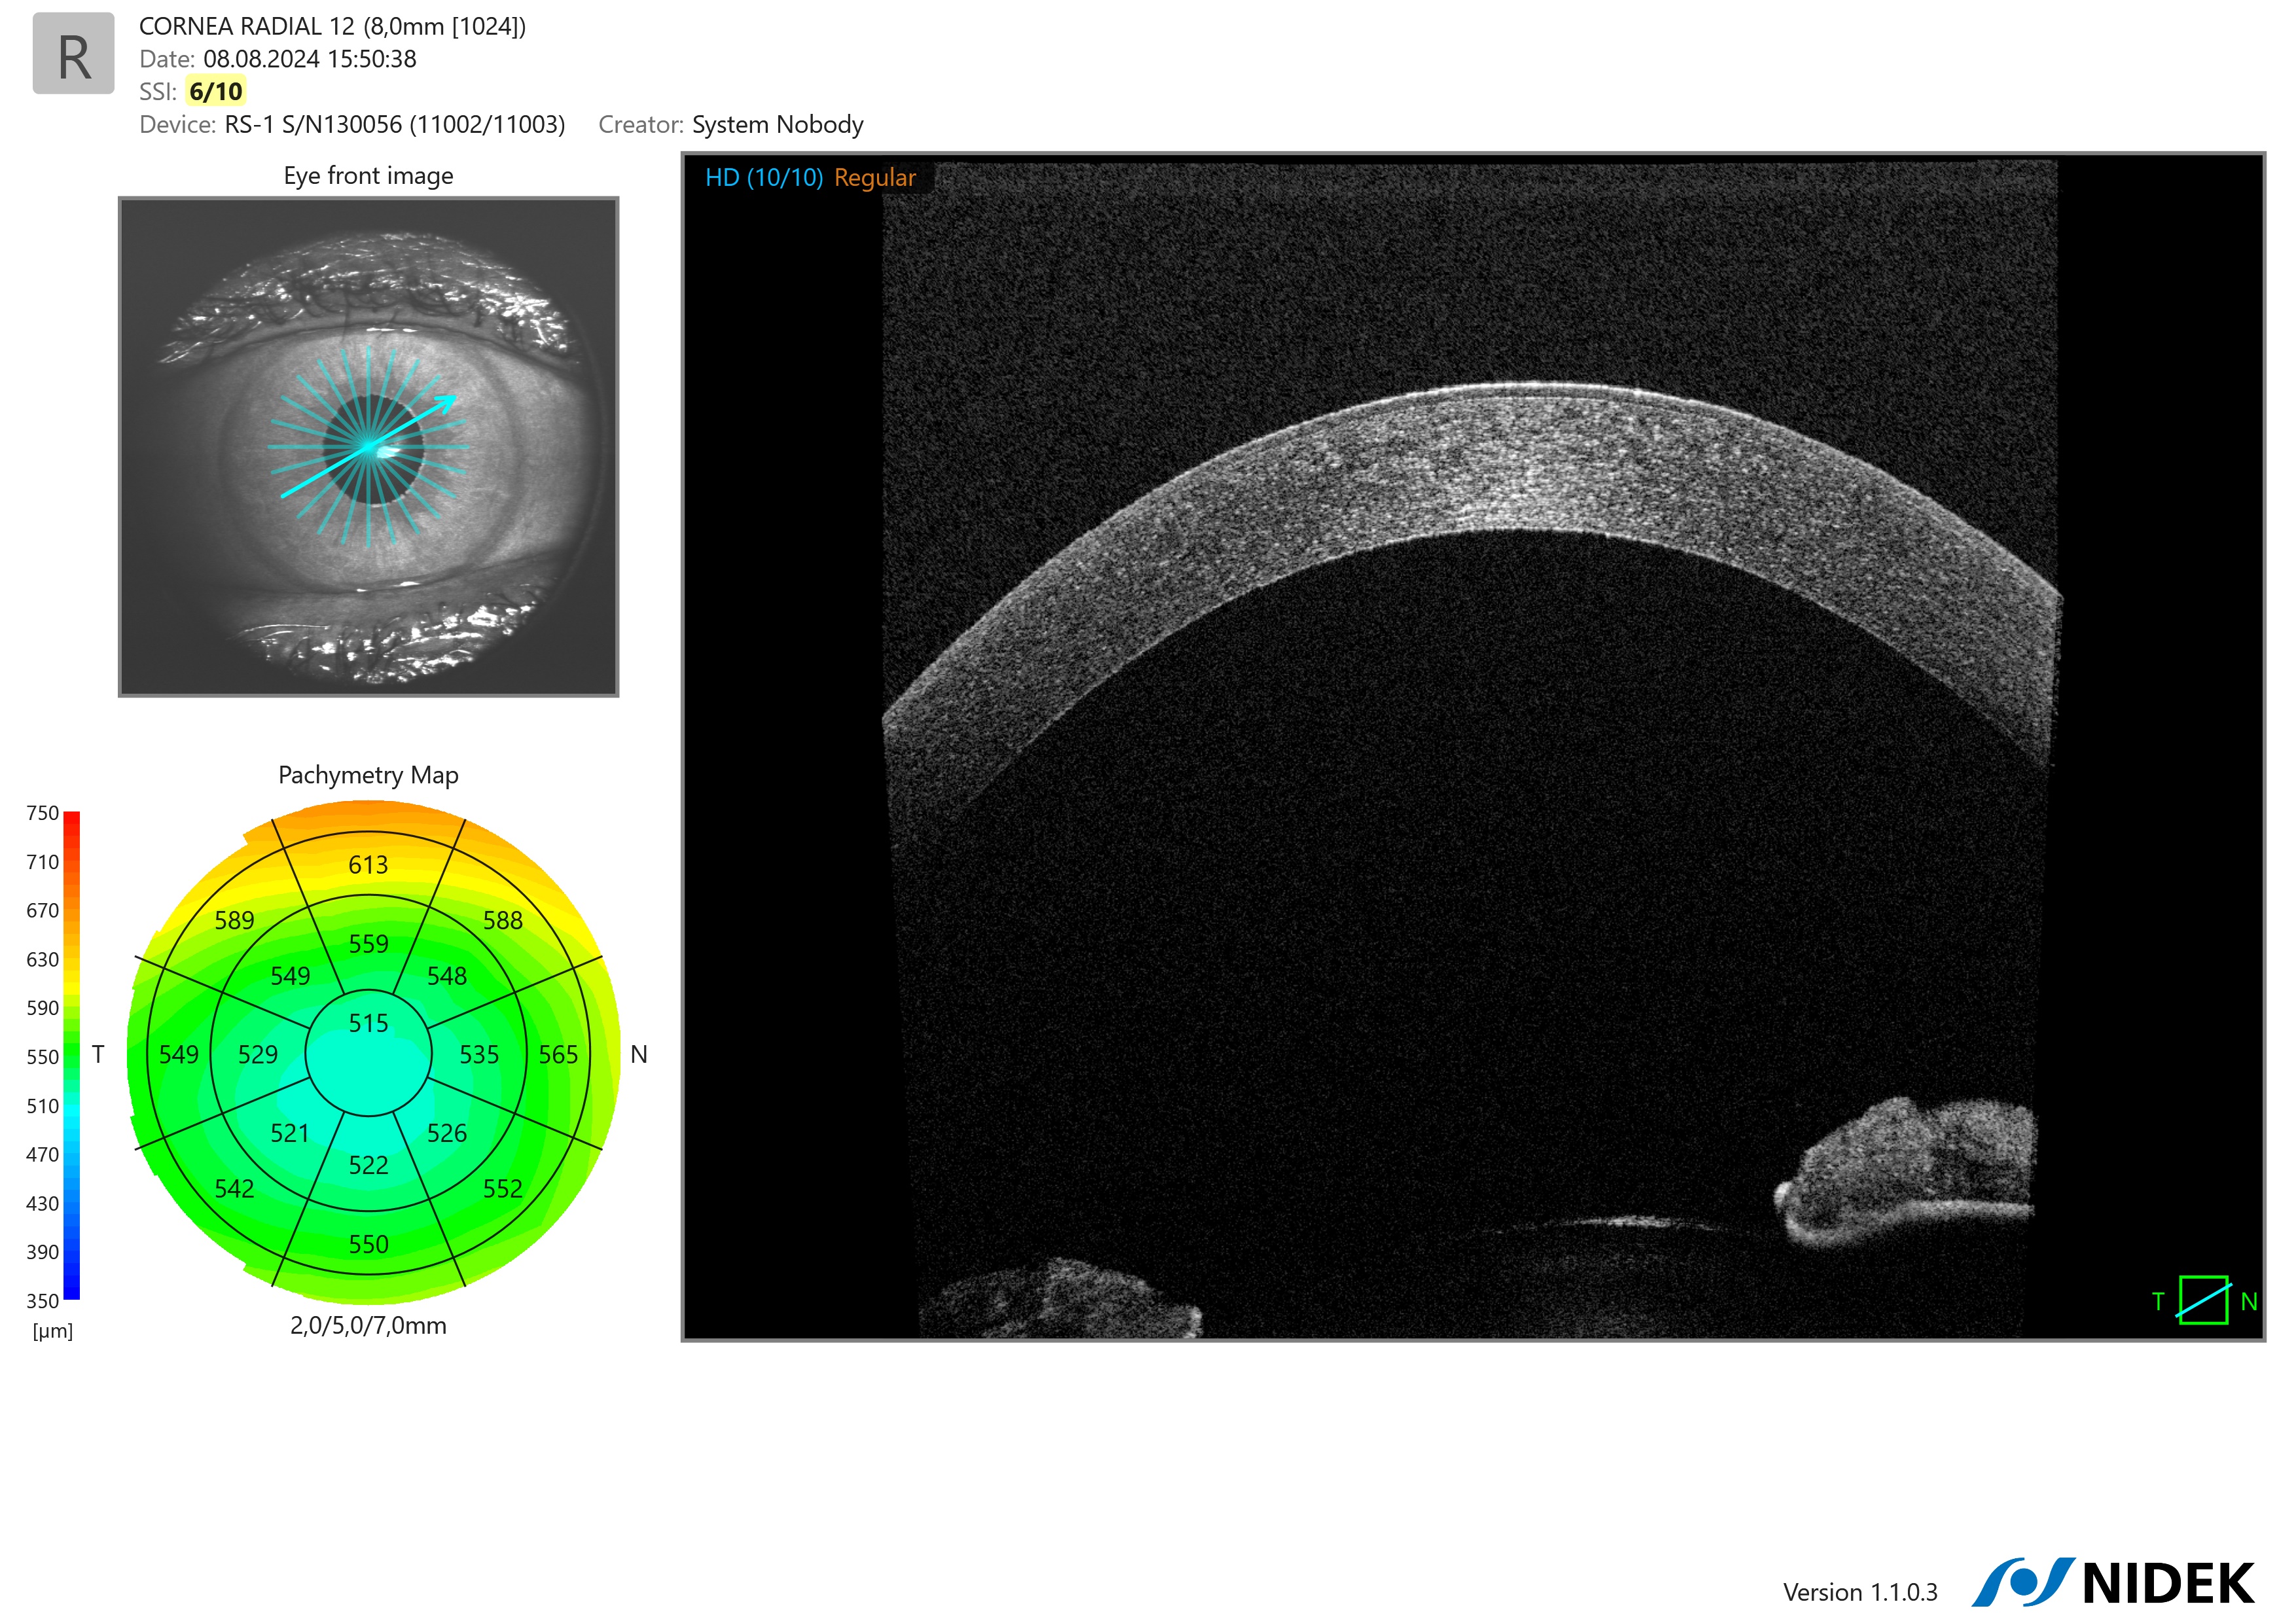

Cornea Radial Pachymetri Map